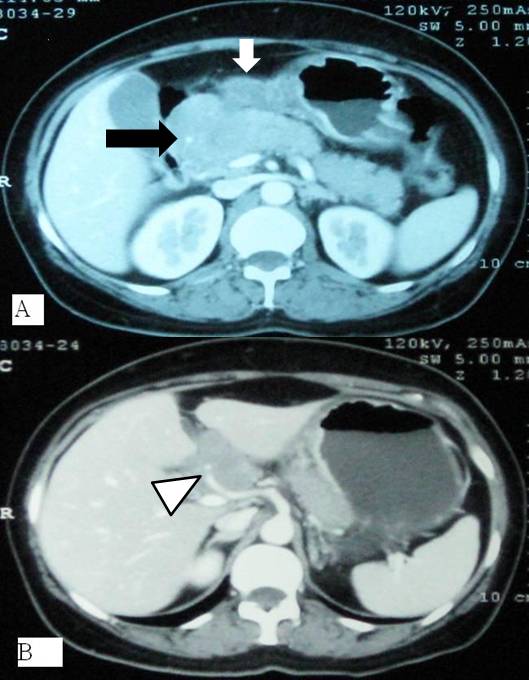

Context Diffuse large B-cell lymphoma is the commonest form of non-Hodgkin lymphoma. Gastro-intestinal tract and bone marrow are common extra-nodal sites of lymphomatous involvement. Case report A 54-year-old woman presented with acute onset epigastric pain. On evaluation, raised serum amylase and radiological features of acute pancreatitis were detected. Gastroscopy revealed thickened folds in distal stomach, which on histopathology revealed large B-cell lymphoma. Subsequently, the patient developed extra-hepatic biliary obstruction due to peripancreatic lymph nodal mass that was relieved with plastic biliary stenting. Subsequent chemotherapy regime directed against lymphoma led to resolution of lymphoma. Conclusion In this patient , pancreatitis was the initial presentation of primary gastric lymphoma, which has not been commonly reported and therefore should be considered in the etiological workup.

Image: Thickened gastric folds in distal body.

Thickened gastric folds in distal body